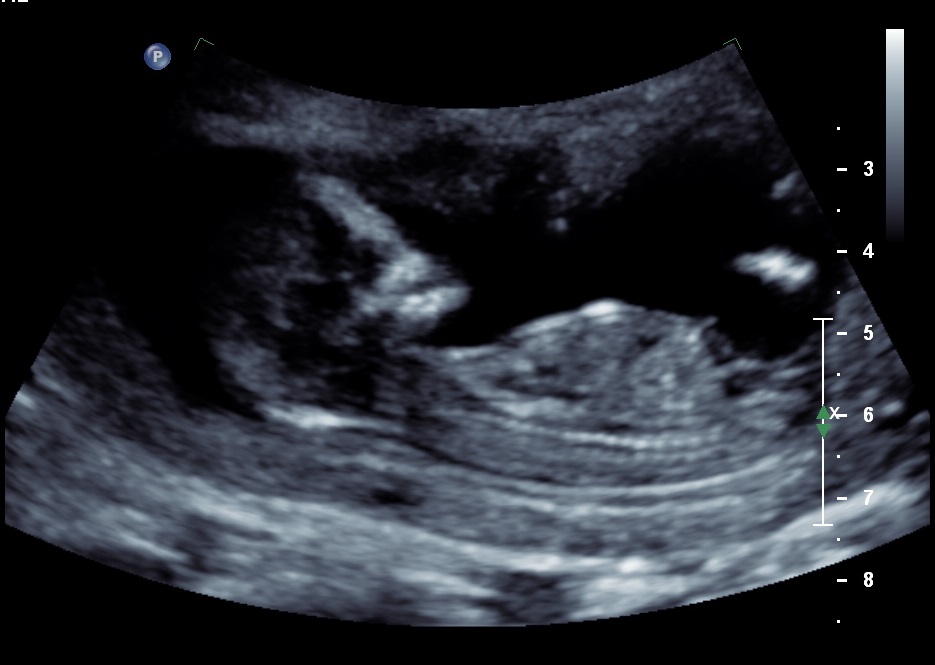

Please help! I am rubbish at reading ultrasounds! Can anyone see the nub and read it for me please? My friend thought she saw it and thought it was a boy angle....but my gut says girl. Hubby isn't letting me find out at the 20w scan so this is the only clue I get!! Thanks so so much.

I'm 12w3d by dates, 13w3d by scan.